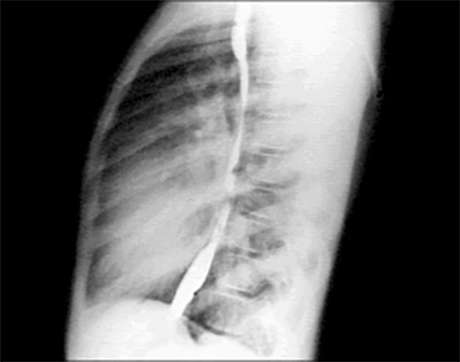

PA and Lateral

Click on the Xrays to enlarge them.

Choose the best interpretation of the chest X rays:

Dilated pulmonary trunk

RV enlargement + dilated

pulmonary trunk +

increased pulmonary vascularity

RV enlargement +

LA enlargement

RV enlargement + small pulmonary trunk +

decreased pulmonary vascularity

Normal